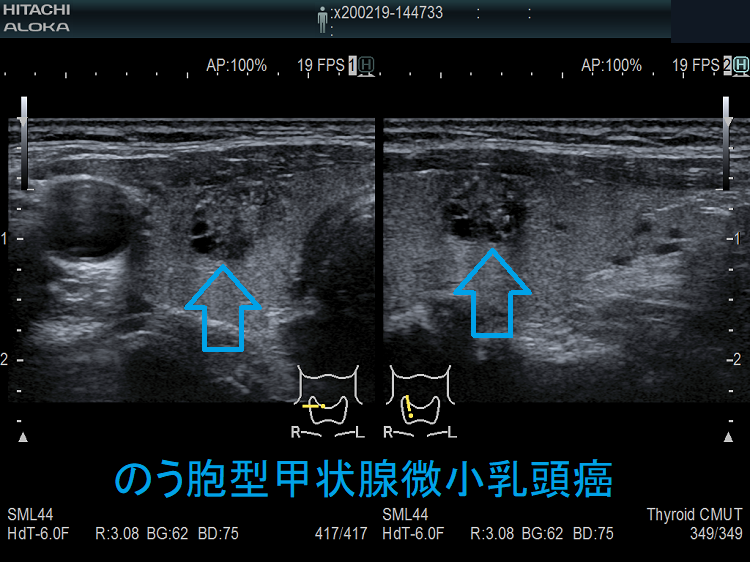

- のう胞型甲状腺微小乳頭癌(嚢胞型甲状腺微小乳頭癌) 超音波(エコー)画像